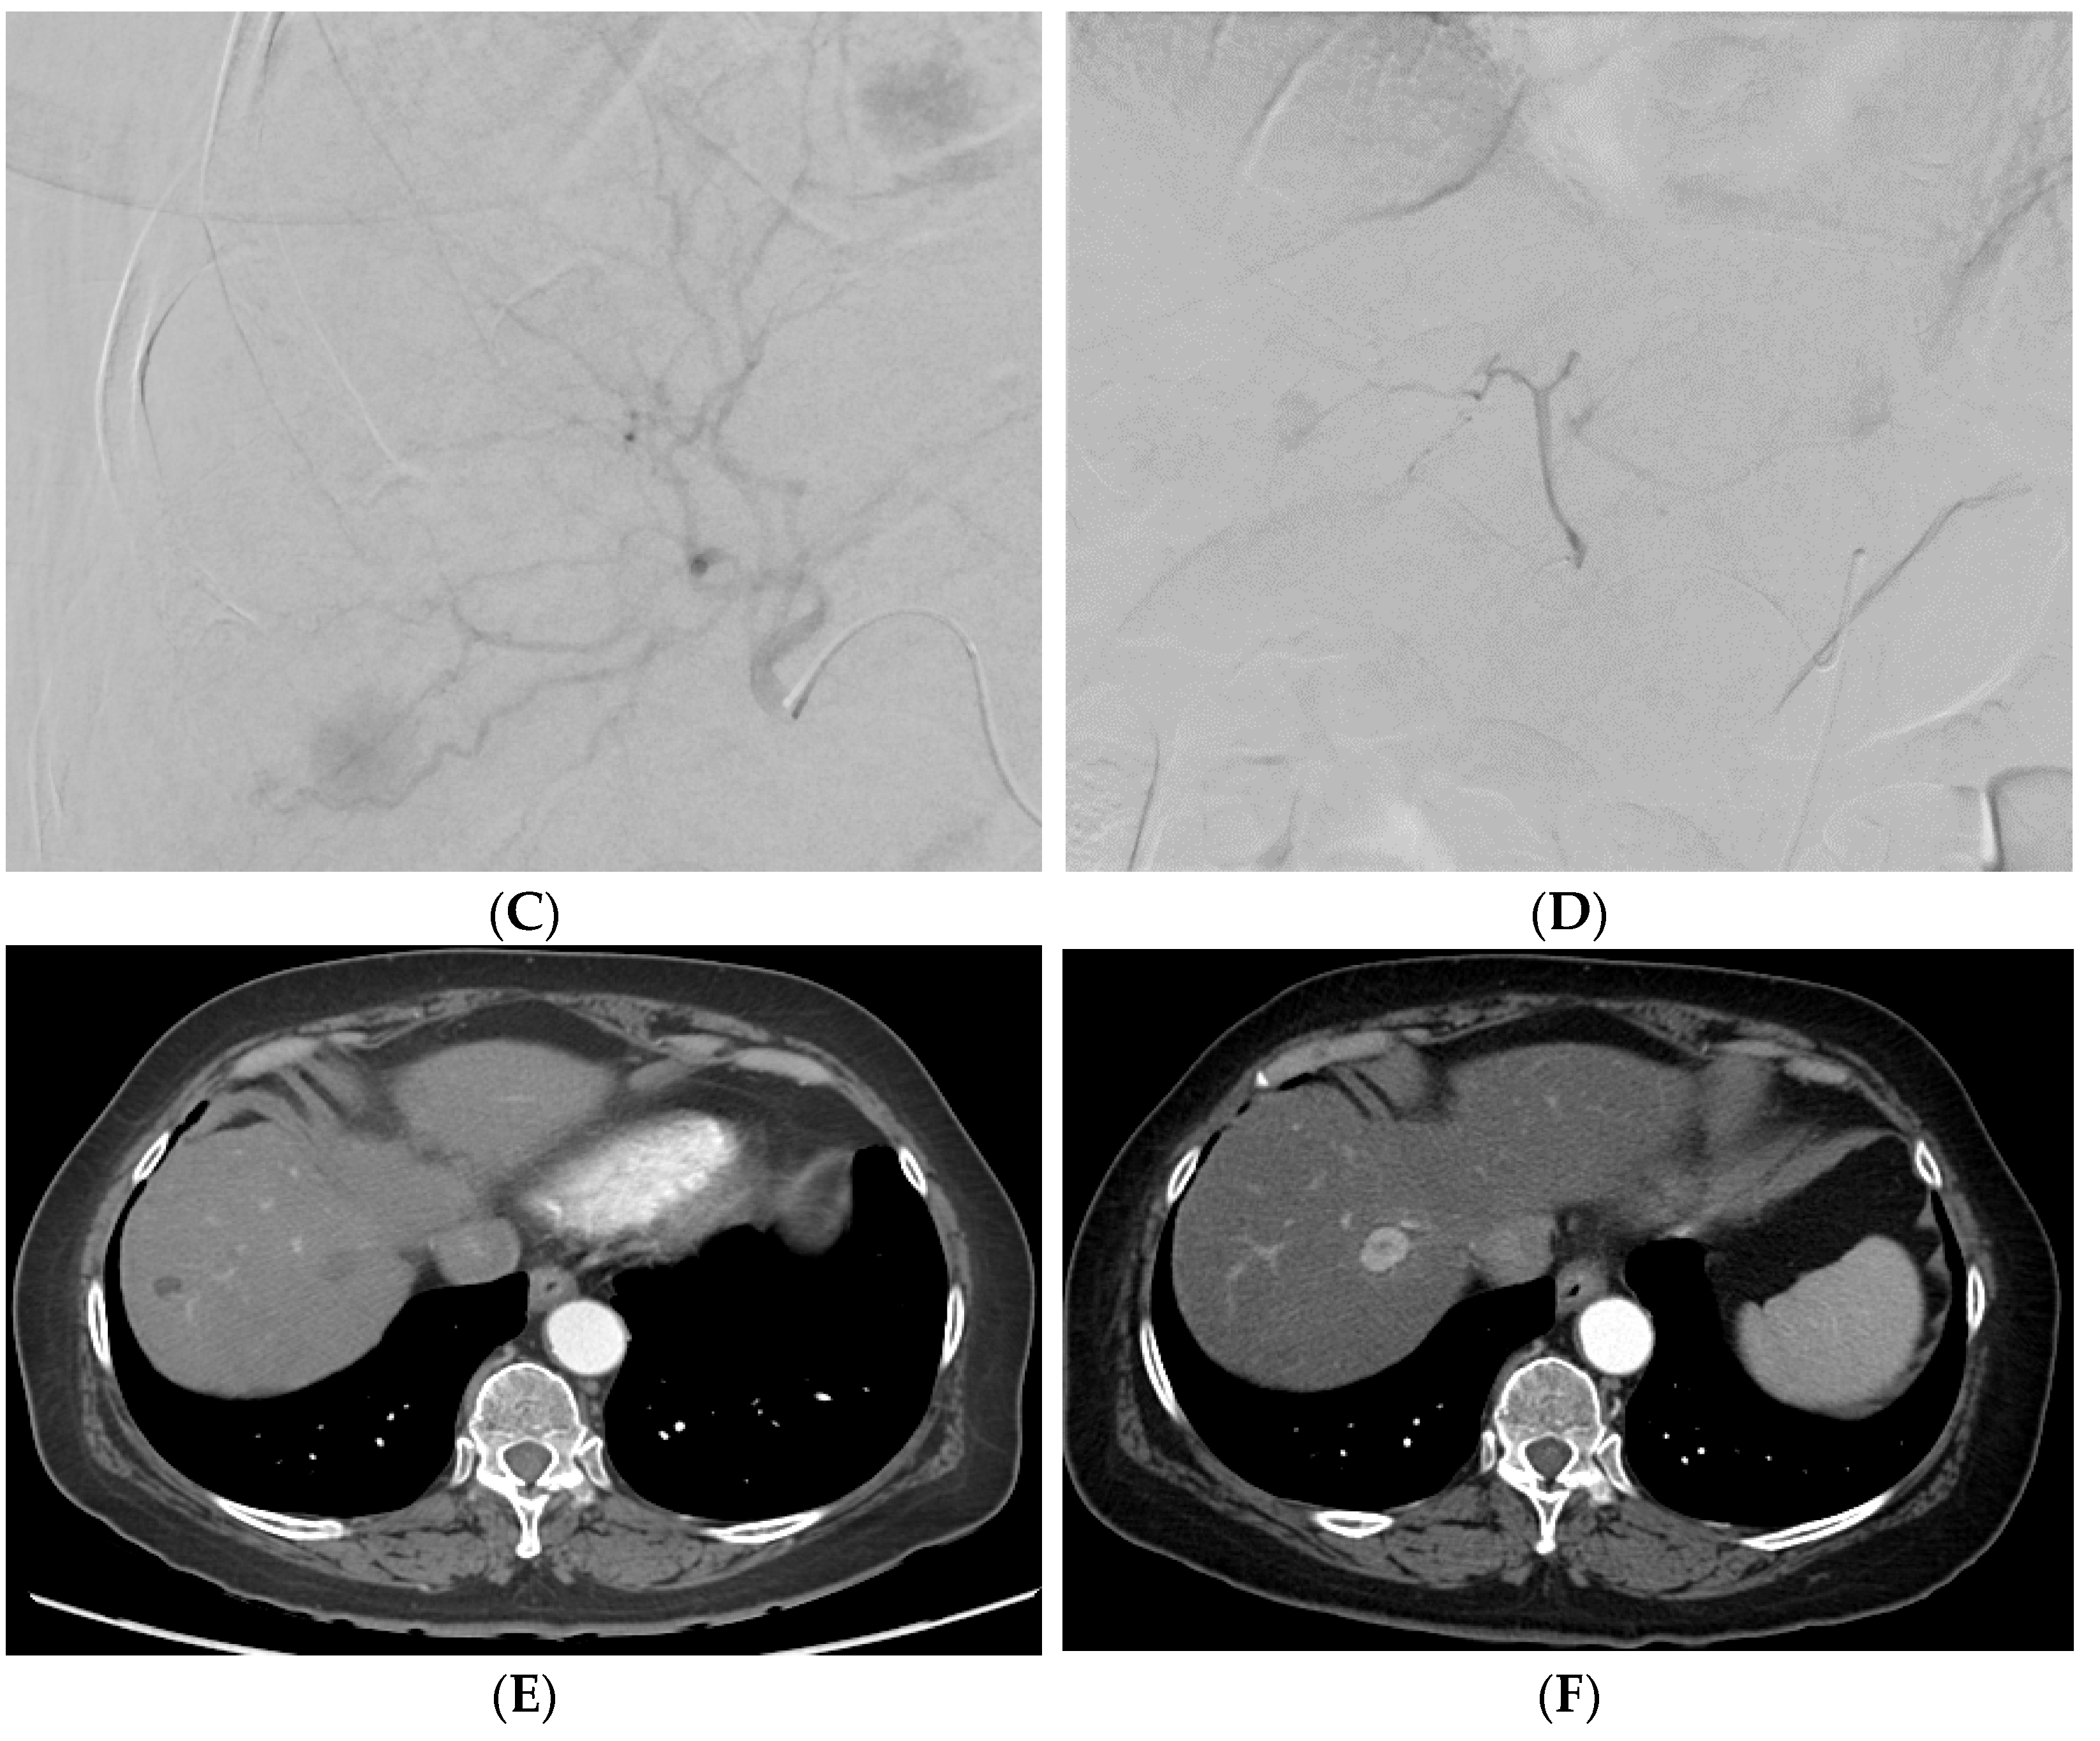

7.2.2. Transarterial Chemoembolization (TACE)

7.2.3. Selective Internal Radiation Therapy (SIRT)

8.2. Transarterial Chemoembolization (TACE)

8.3. Drug-Eluting Beads–Transarterial Chemoembolization (DEB–TACE)

12.1. Imaging Response Criteria